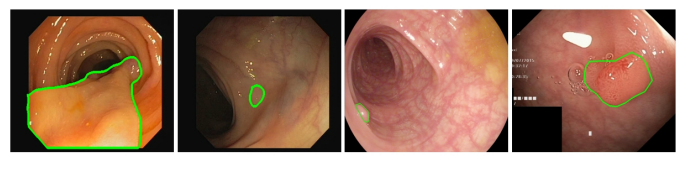

三、结直肠息肉分割

(1)基于双域特征融合的息肉分割算法

结肠直肠癌是全球发病率最高的癌症之一,也是导致癌症死亡的主要原因之一。结直肠癌通常起源于结肠或直肠内的腺瘤性息肉,并在数年内逐步形成。研究发现,早期发现和切除息肉对预防结肠直肠癌至关重要。因此,开发具有计算机辅助手术系统的自动手术机器人变得非常重要。结肠镜检查广泛用于结直肠癌筛查,能够提供息肉的位置和外观信息。息肉分割作为一项重要的任务,可以为计算机辅助手术系统提供息肉位置。然而,由于息肉外观多样且背景复杂,在结肠镜图像中准确分割息肉具有挑战性。因此,设计一种更鲁棒的息肉分割方法是迫切的。

图5 息肉结肠镜检查图像示例